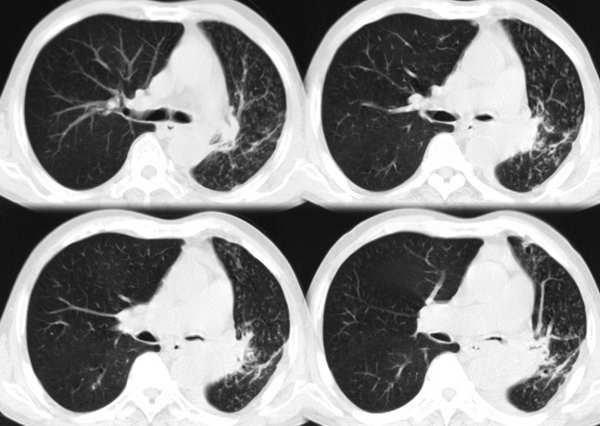

m67y外院ct诊断肺ca,现来我科复查ct

左肺下叶支气管狭窄局部见肿块影左肺下叶不张,肺癌应该没问题吧

典型中央型肺ca

左主支气管变窄,左下叶部分不张,考虑肺癌可能性大

考虑左下肺中央型肺癌并肺不张,建议支气管镜检查。

左下肺中央型肺癌并不张可能性大,为慎重起见,请楼主提供病史,以排除支气管内膜结核引起肺不张。

左中央型肺癌并左下叶肺不张,建议纤支镜检查.

左下肺中央肺ca并下肺不张